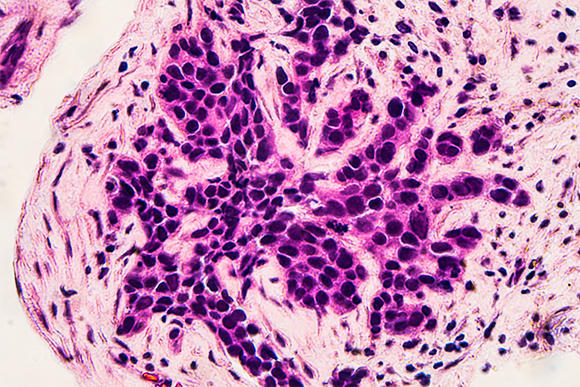

גילוי מוקדם משפר את סיכויי ההחלמה מסרטן שד. תמונת מיקרוסקופ של תאי סרטן מביופסיה שנלקחה בעקבות בדיקת ממוגרפיה | צילום: David A Litman, Shutterstock